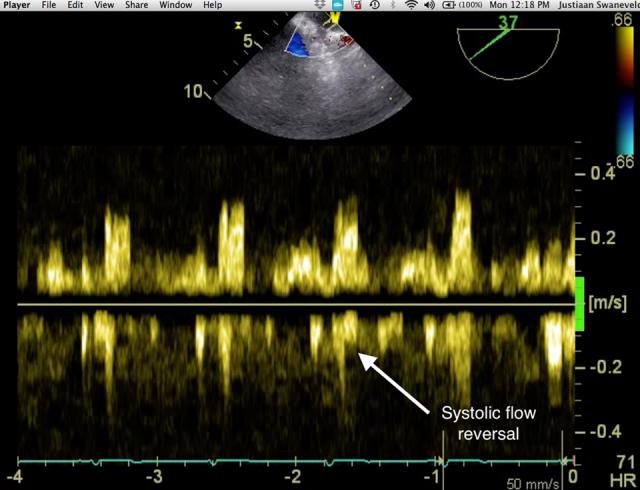

Transoesophageal echocardiography (TOE) has, in certain clinical situations, become an almost universal monitor and diagnostic tool. In the perioperative environment, TOE is frequently used to guide anaesthetic management and assist with surgical decision making for, but not limited to, cardiothoracic, major vascular and transplant operations. The use of TOE is not limited to the theatre environment being frequently used in outpatient clinics, emergency departments and intensive care settings. Two case reports, one of oesophageal perforation and another of TOE utilization in a patient having previously undergone an oesophagectomy, introduce the need for care while using TOE and highlight the need for vigilance. The safe use of TOE, the potential complications and the suggested contra-indications are then considered together with suggestions for improving the safety of TOE in adult and paediatric patients.

在某些临床情况下,经食管超声心动图(TOE)已几乎成为一种通用的监测和诊断工具。在围手术期环境中,TOE经常用于指导麻醉管理,并协助进行手术决策,适用于但不限于心胸、大血管和移植手术。TOE的使用并不局限于手术室环境,在门诊诊所、急诊科和重症监护环境中也经常使用。两篇病例报告,一篇是食管穿孔,另一篇是在一名先前接受过食管切除术的患者中使用TOE,介绍了使用TOE时需要谨慎的情况,并强调了警惕的必要性。随后将一起考虑TOE的安全使用、潜在并发症和建议的禁忌症,以及提高成人和儿童患者TOE安全性的建议。